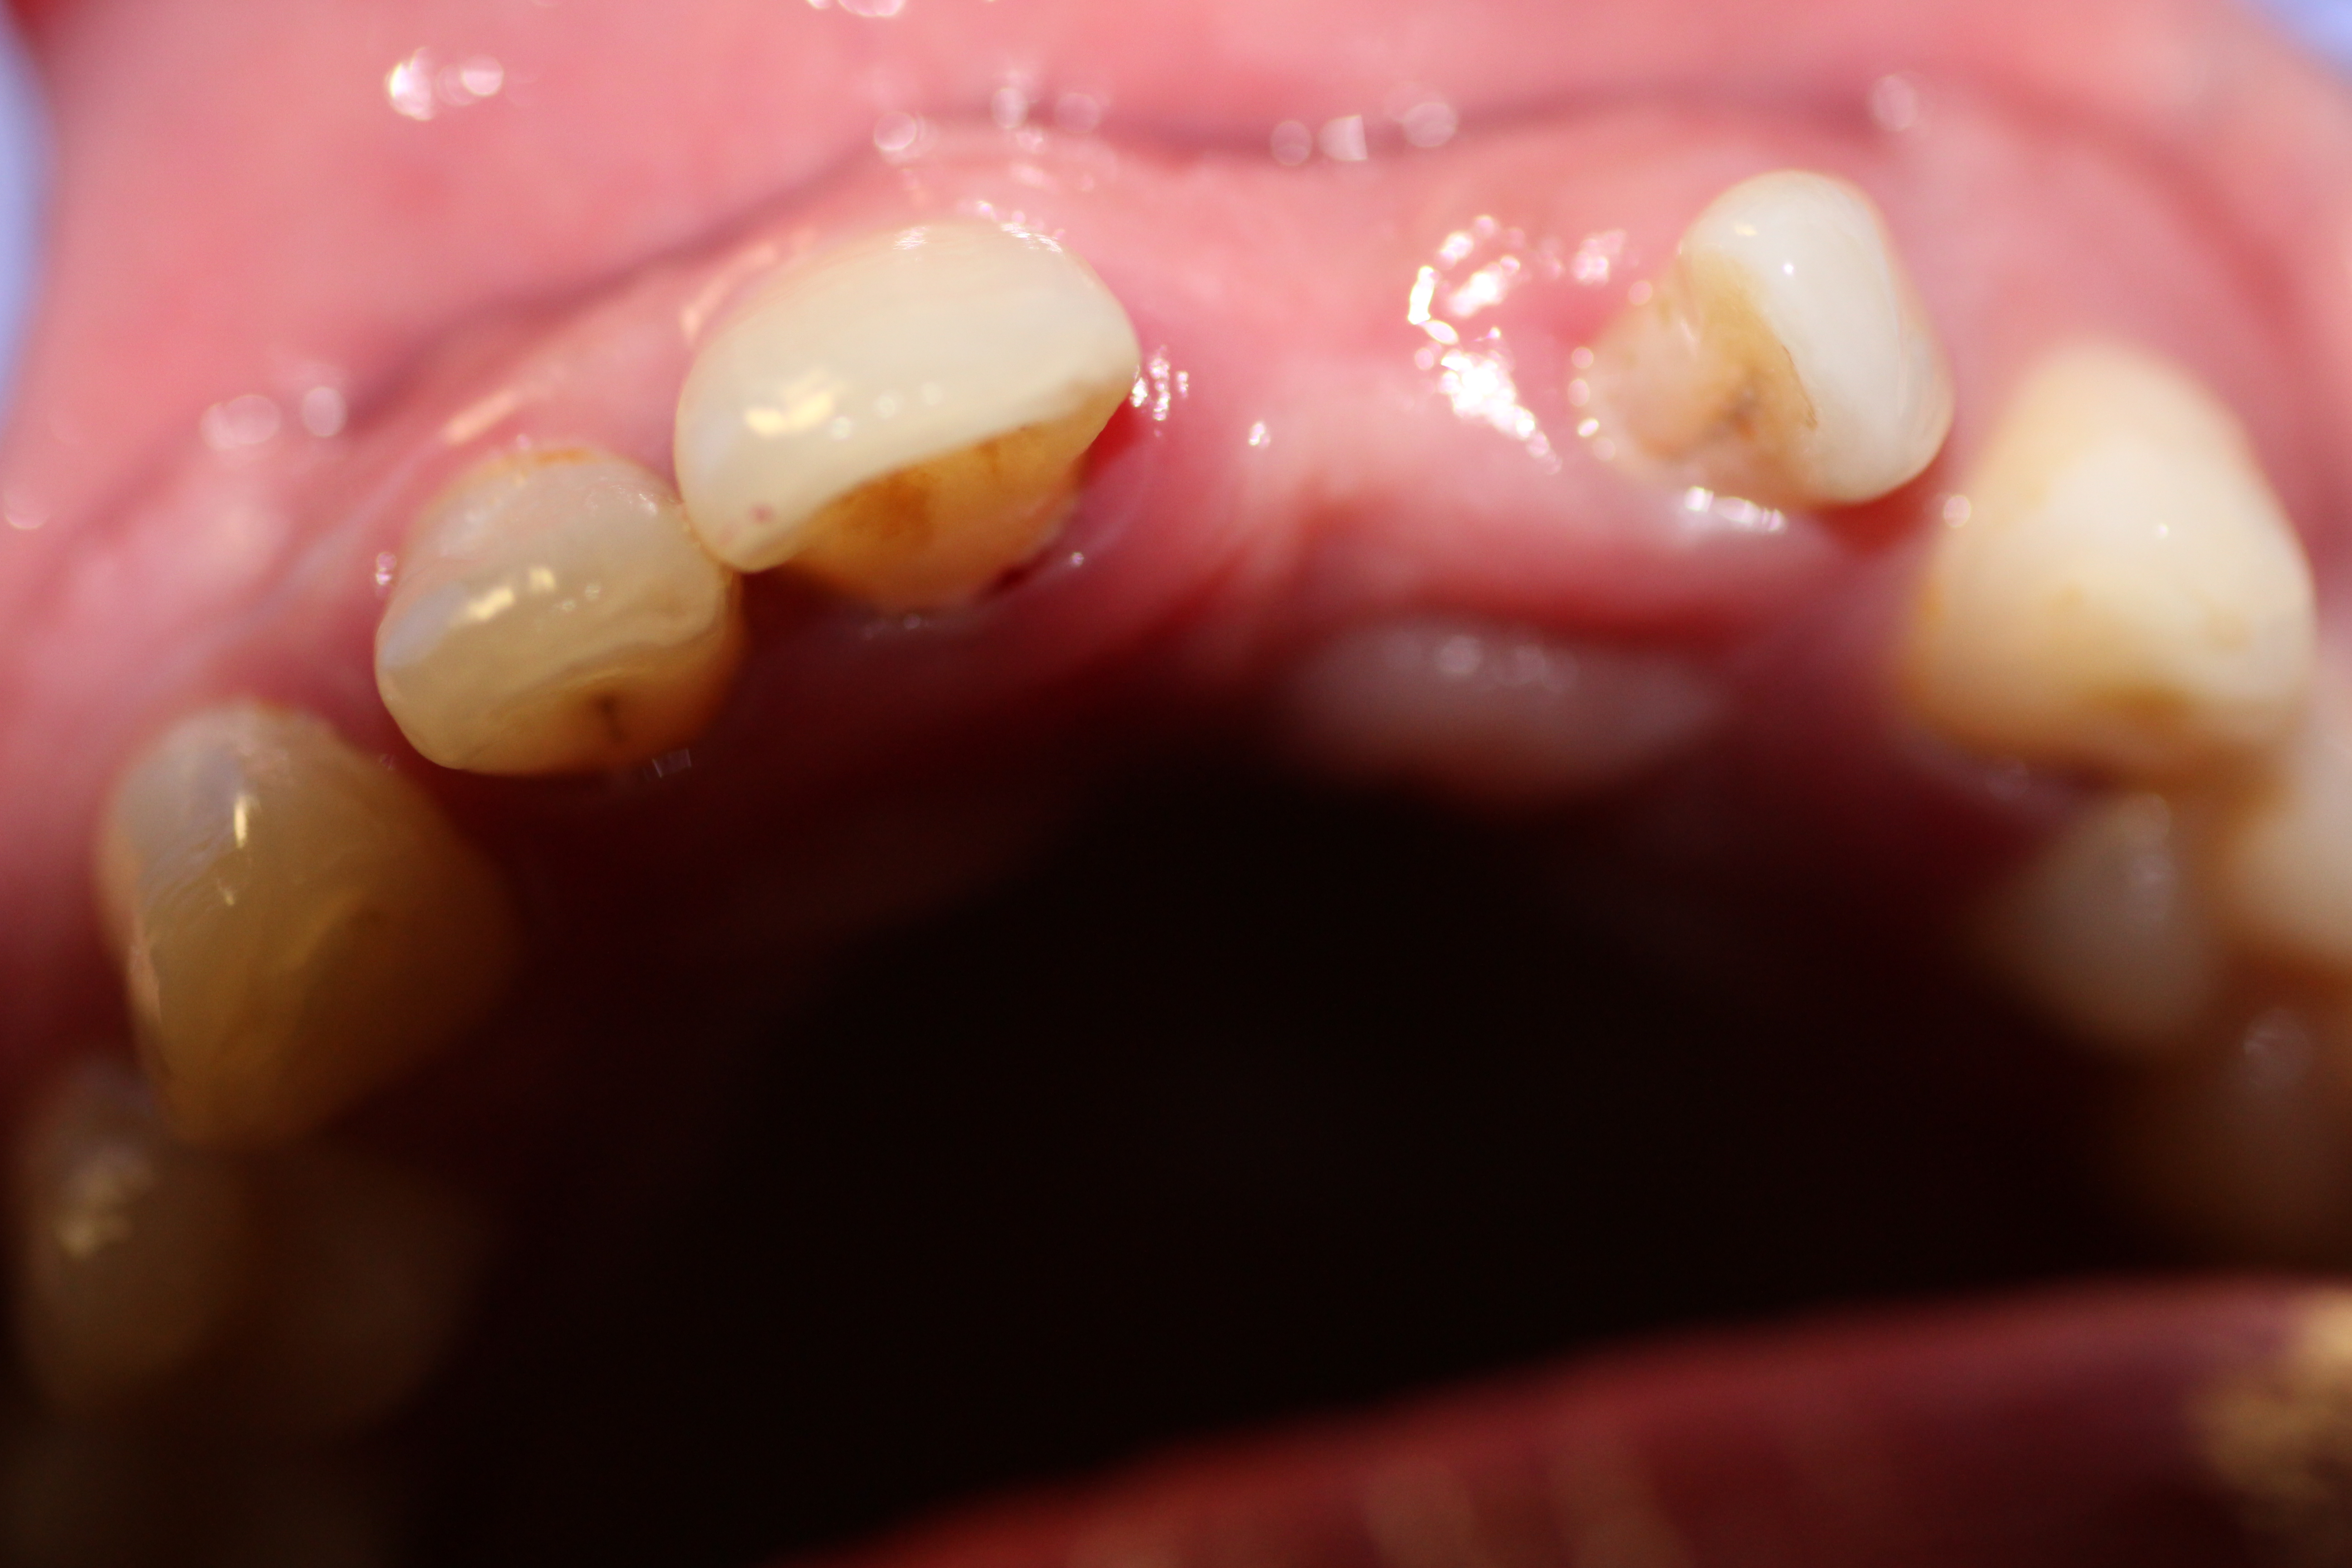

- Before Surgery.

-